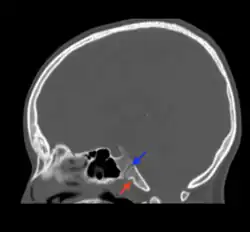

Fossa navicularis magna (also known as pharyngeal fossa or phyaryngeal fovela) is a variant bony depression found at the midline of the occipital part of clivus. This fossa was first described by Tourtual.[1] Its prevalence ranges from 0.9 to 5.3%.[2]

Fossa navicularis magna is located on the anterior surface or pharyngeal surface of the clivus. Its position when present is between the spheno-occipital synchondrosis and the foramen magnum. Size of this fossa varies considerably and its depth ranges from 3.49 to 4.94 mm.[3] A histological study reported the presence of loose connective tissue containing collagen and elastic fibers within the fossa navicularis magna.[4]